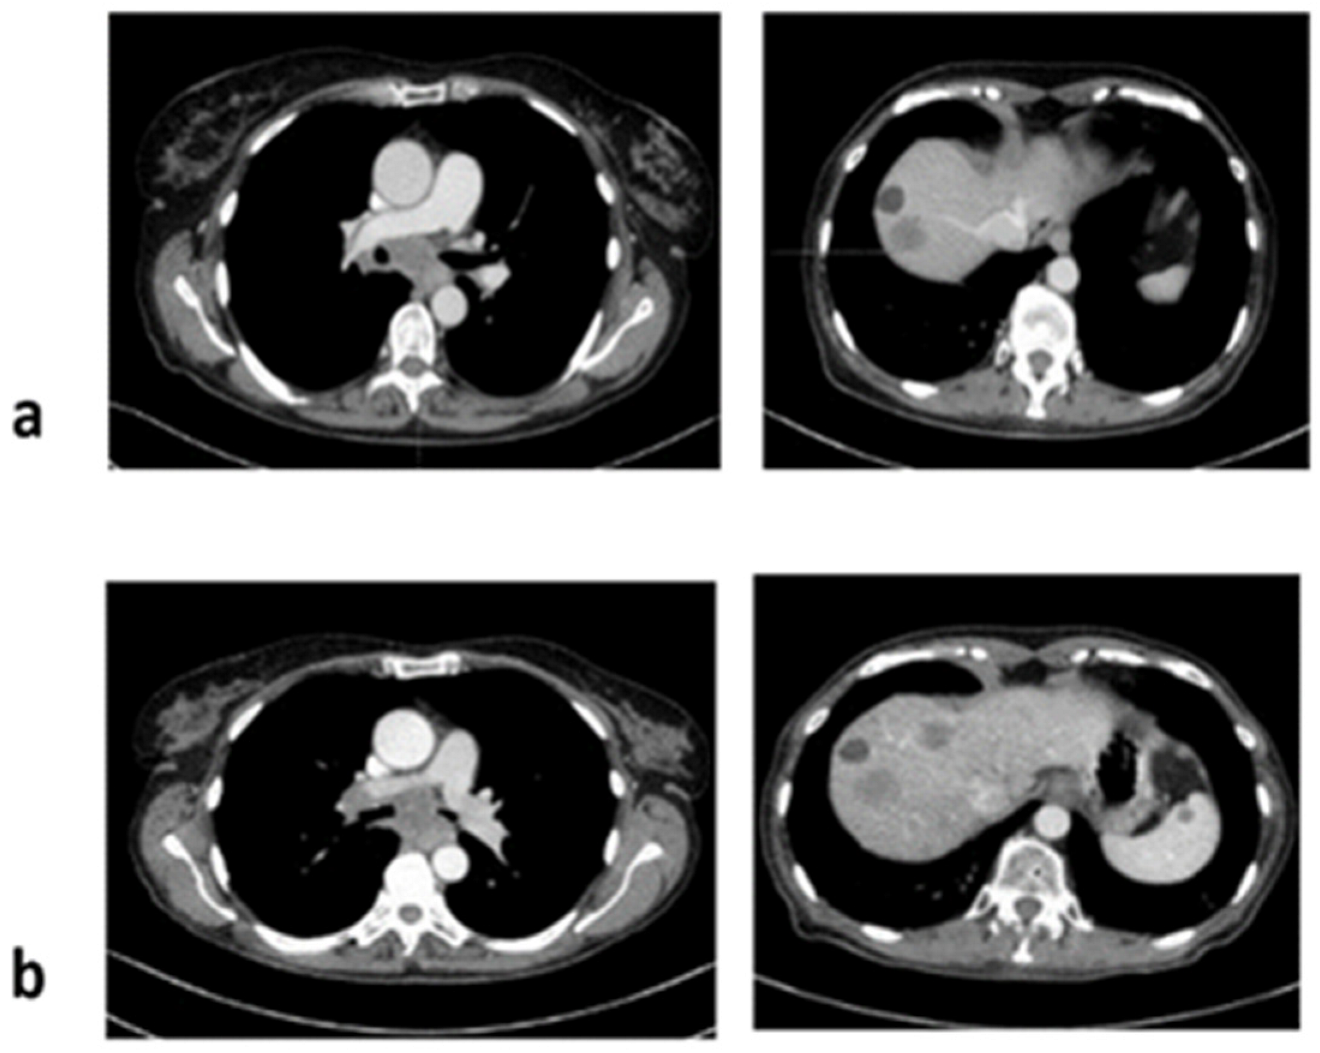

3. Case 2